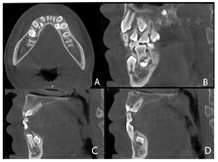

。CBCT示11牙根向远中明显弯曲,牙根发育至Nolla9期;21牙根发育至Nolla9期,腭侧见两颗正置锥形多生牙,牙根未发育完成;12、22牙根发育至Nolla9期;23牙冠近中倾斜至62根方。

根尖片示:11自根中向远中弯曲约35°,属Ⅱ类弯曲牙,牙根发育至Nolla9期,21牙根发育至Nolla9期,腭侧见两颗正置锥形多生牙;12、22牙根发育至Nolla9期。

CBCT示:上颌恒牙胚萌出间隙不足,根据Moyers混合牙列分析法,牙弓现有长度为177.4 mm,牙弓应用长度为181.6 mm,拥挤度为4.2 mm。42缺失;11、21、22发育至Nolla9期;55、16、65、46冠部低密度影及牙本质中层,根管内未见高密度充填影,根尖周未见明显异常。53、63牙根吸收不足1/3,13、23发育至Nolla8期。

2020年12月21日口腔颌面部CBCT精确定位、笑气镇静+4%肾上腺素-盐酸阿替卡因注射液局部浸润麻醉下先行拔出恒中切牙腭侧多生牙,同期切除部分牙龈暴露双侧上中切牙牙冠最宽径。4个月后11仍未有萌出迹象,21萌出,与31反